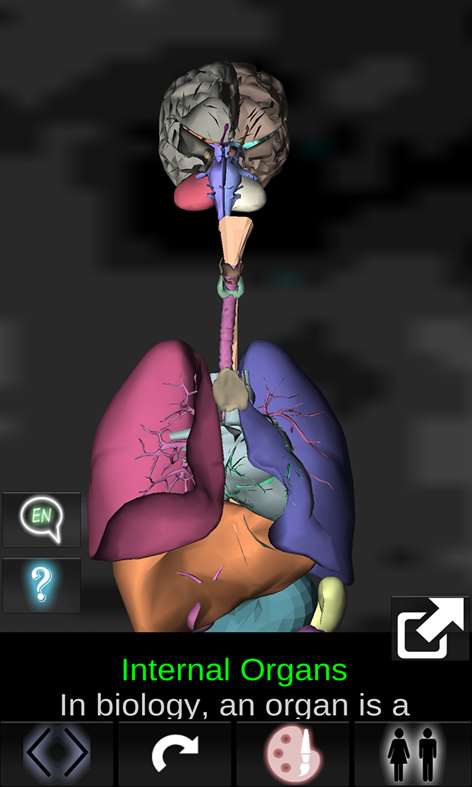

Shows a three-dimensional model of the human body organs and a description of all of them. This application is intended to complement the study of anatomy in medicine, biology or other. Touching each organ as the heart, brain, lungs, reproductive system, liver, intestine, ovary, testis, stomach, kidney, etc.. information is displayed. Practical, useful and valuable anatomical information in your palm. Reference to primary education, secondary school, college or culture in general.